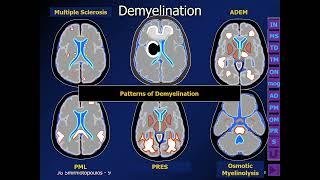

️ Making Sense of White Matter Disease by James G. Smirniotopoulos, M.D.

Educational Symposia

6K

20,476

2 года назад